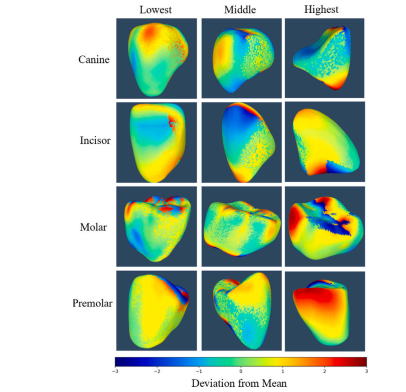

Fig. 7. Color maps showing the signed distance (in mm) between predicted andground-truth 3D meshes for four tooth types — Canine, Incisor, Molar, and Premolar— each visualized at low, median, and high deviation levels. Positive values indicatemesh overestimation, and negative values indicate underestimation. Canines (tooth 43,13), Incisors (tooth 31, 11), Molars (tooth 46, 16), and Premolars (tooth 14, 15) revealvarying degrees of alignment accuracy, with notable discrepancies in complex regions.The analysis ranges from −3 to +3 mm, highlighting model performance across diversedental structures.

图7:彩色图谱展示了四种牙齿类型(尖牙、切牙、磨牙和前磨牙)的预测三维网格与真实三维网格之间的有向距离(单位:毫米),每种牙齿类型均在低、中、高偏差水平下进行可视化呈现。正值表示对网格的高估,负值表示对网格的低估。尖牙(牙齿43、13)、切牙(牙齿31、11)、磨牙(牙齿46、16)和前磨牙(牙齿14、15)显示出不同程度的对齐精度,在复杂区域存在明显差异。分析范围为-3毫米至+3毫米,突出了模型在不同牙齿结构上的性能表现。